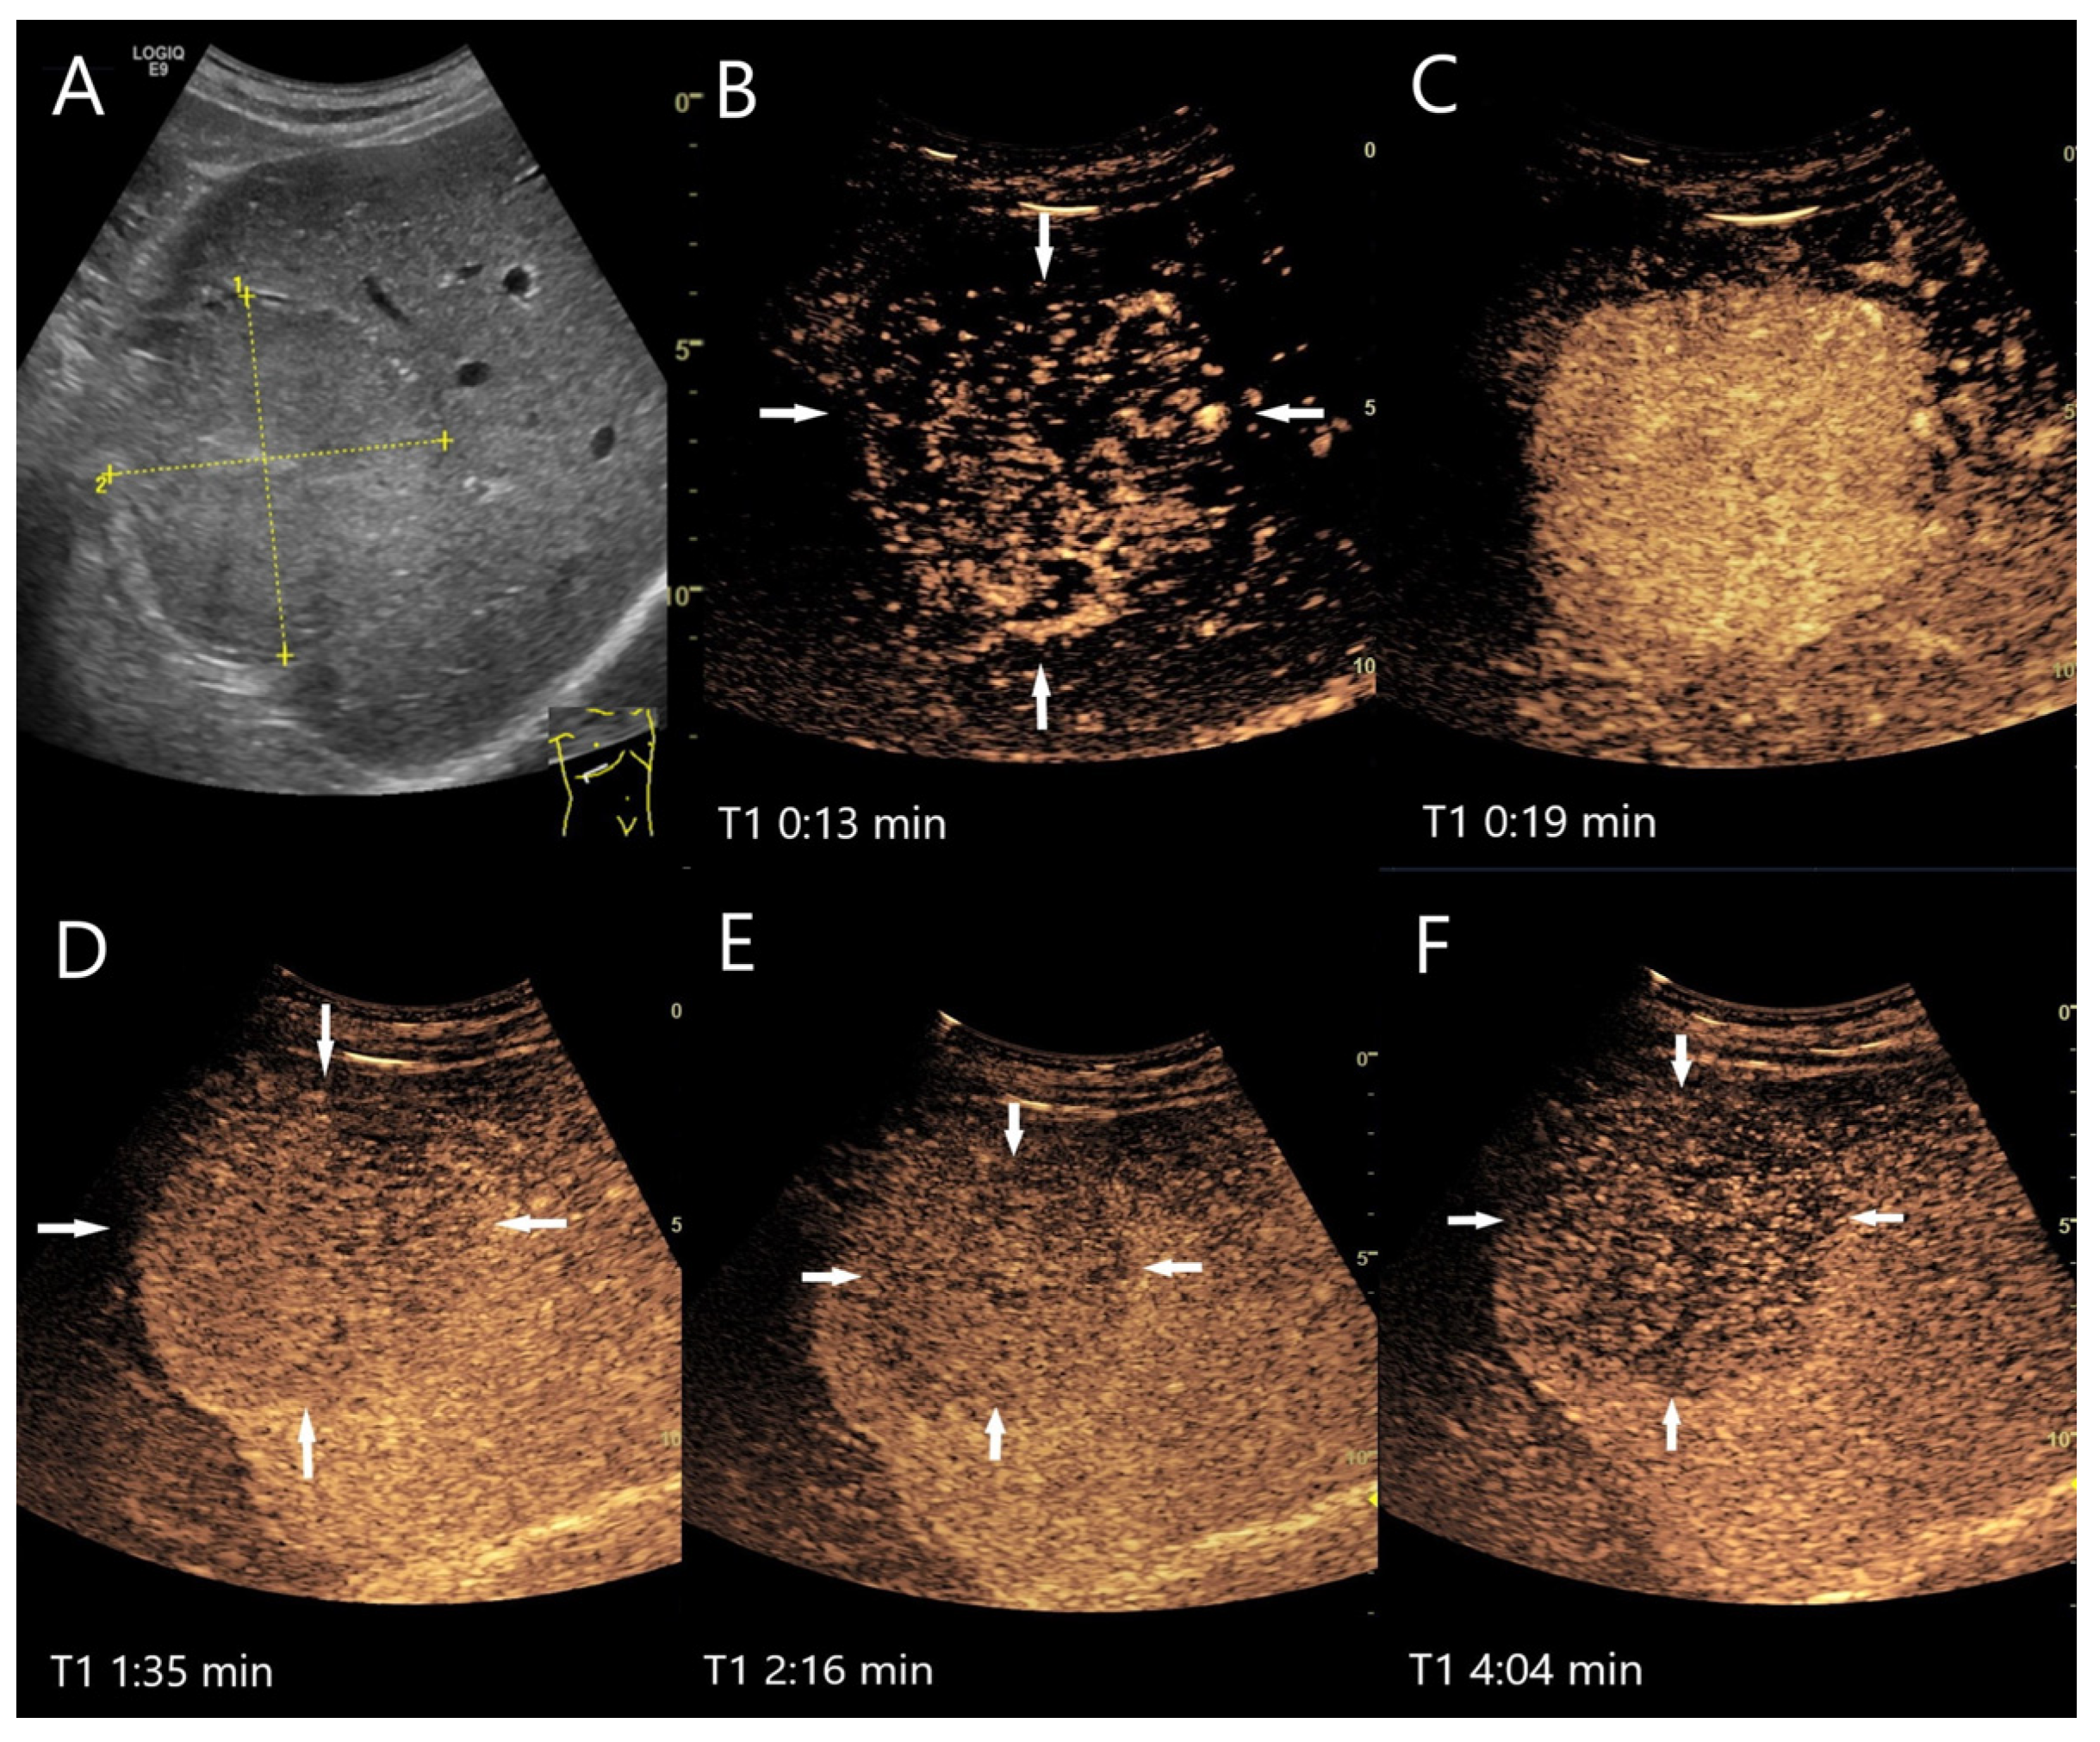

| Abscesses | Hypo-/anechoic. | Hyperenhancement in phlegmonous stage, transient hyperenhancement in surrounding parenchyma. Non-enhancement of necrotic parts. Honeycomb sign. | Early washout. | Formation of thromboses of the small hepatic and portal veins, as well as pylephlebitis of the small portalvenous vessels. |